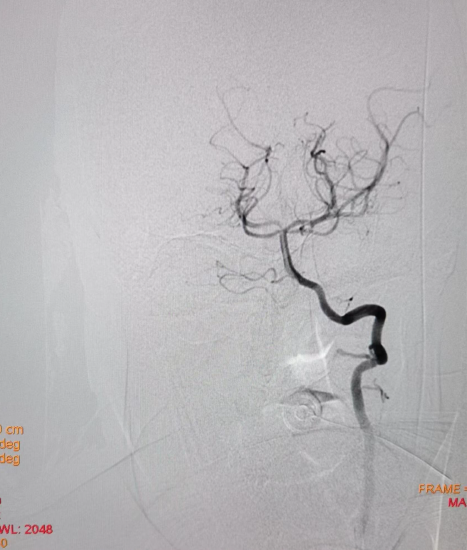

过程影像

病历夹什么径技·第152期|串联营病历夹:川陕大营_https://www.jmylbn.com_新闻资讯_第88张

接下来处理远端,Synchro微导丝与Rebar微导管的辅助下,选择置入Solitaire(4-20)支架,支架打开后使用抽拉结合的方式使血管再通。

病历夹什么径技·第152期|串联营病历夹:川陕大营_https://www.jmylbn.com_新闻资讯_第89张

取栓后造影如下:

手术评估

病历夹什么径技·第152期|串联营病历夹:川陕大营_https://www.jmylbn.com_新闻资讯_第90张

病历夹什么径技·第152期|串联营病历夹:川陕大营_https://www.jmylbn.com_新闻资讯_第91张

病历夹什么径技·第152期|串联营病历夹:川陕大营_https://www.jmylbn.com_新闻资讯_第92张

<<滑动查看下一张图片>>